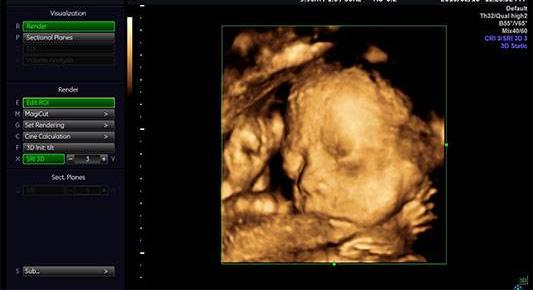

四维超声则是在三维彩超的基础上增加了时间维度,通过三维容积探头连续采集图像,同时进行同步立体图像的数据处理,获得实时动态的胎儿的立体结构图像,能实时捕捉到胎儿的运动,可有效筛查胎儿畸形。

可见,四维超声只是超声检查的一个技术,并非是一个检查项目,这种技术可运用到超声检查的不同项目中,当然也包括胎儿畸形的筛查,也就是大家经常讲的“孕期大排畸”。

当然,很多医院也为了迎合孕妈妈的心理,大家都想知道胎儿的长相,留下一张胎儿的纪念照片,所以好多医院所宣传的四维彩超,其实只是将胎儿系统彩超检查中的一个三维图像打印出来而已,也就变成了大家所说的胎儿四维彩超了。